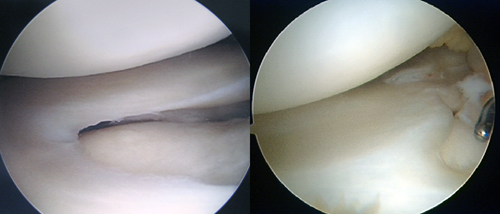

左:正常な半月板 右:円盤状半月板